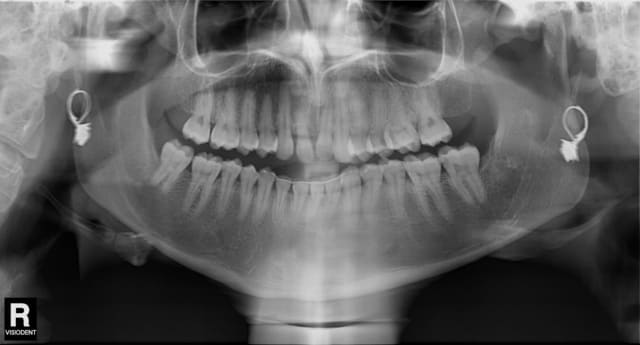

- 11 : extraction et implantation 11 rhyzalysée et mobile

Espaces mesio distaux : 8mm

Prévus implant Zimmer (finir les stocks) ou Legacy (j'en vois déja un venir...:) ) de 4,1 mm ou 4,2, longueur au moins 11,5 faisable

Pano znwidz - Eugenol

Penses quand même à traiter 37

Pour 37, il faut que je vérifie ! Merci j'etais concentré sur 11/21

Par contre par rapport à ça, j'ai souvent eu des images à la pano type carie au niveau des points de contacts, qui n'ont pas été confirmées à la retro et à l'examen clinique...